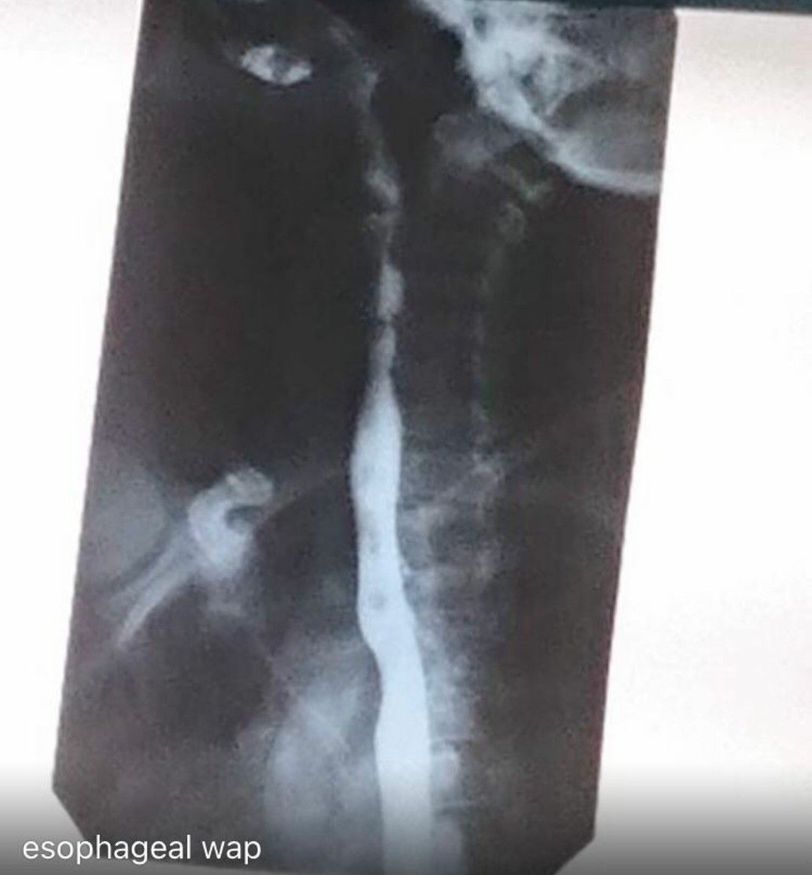

Plain film x-ray indication barium swallow The Patient came esophagel wep clinical feature dysphagia and esophageal web characrazed of plummer Vinson syndrome severe iron deficiency and esophageal web and red tongue 👅 atrophy beefdy,glossitis and dysphagia